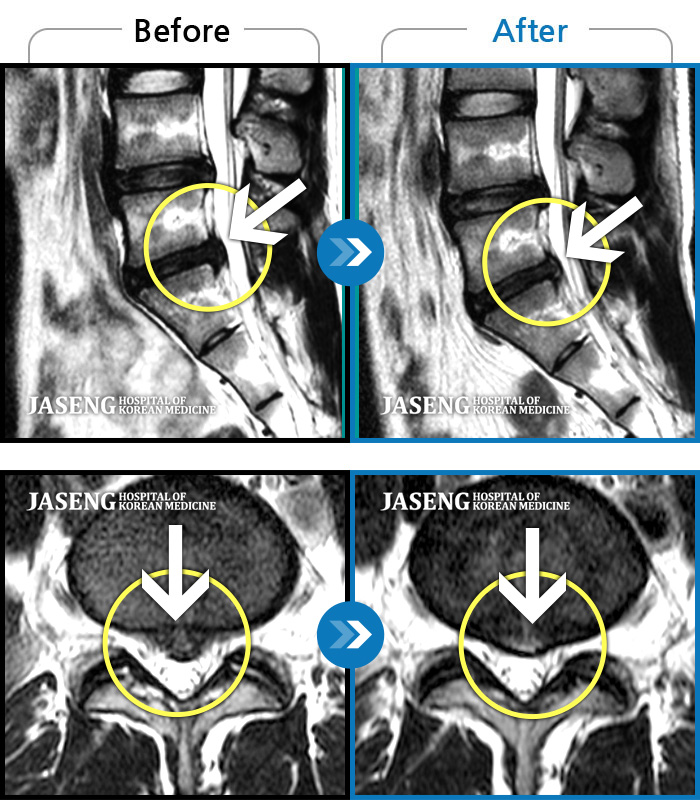

허리디스크

강남 · 이남우 원장

좌측 다리 저림 증상이 너무 심하여 앉거나 서는 것이 안되고 다리를 들어올릴 수 가 없었다.

촬영시기

2023.05.09 ~ 2023.12.12